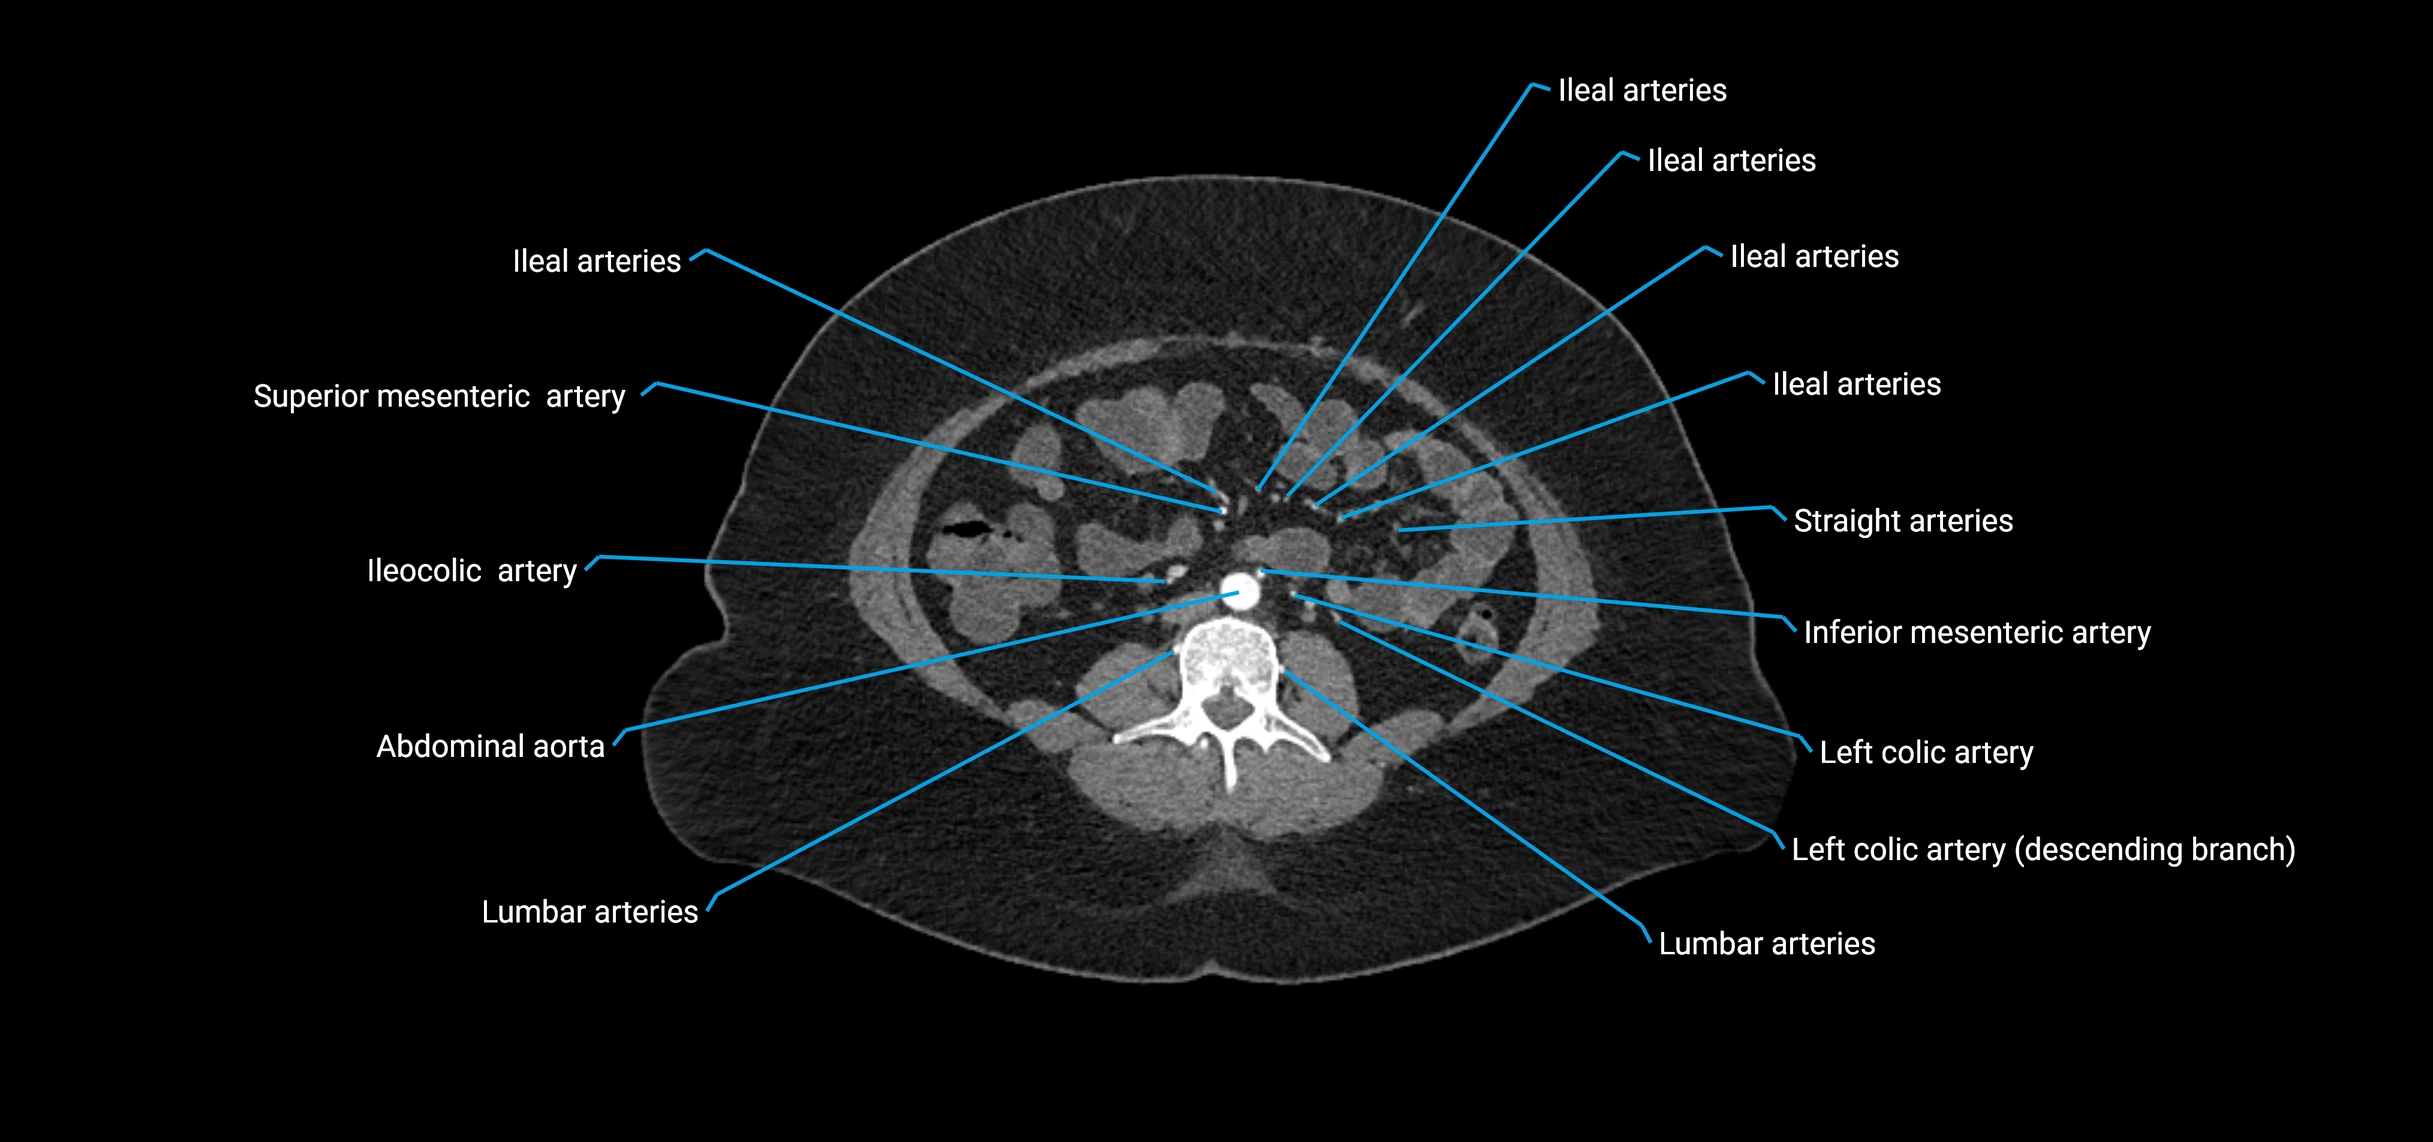

Branches

• Unpaired visceral branches: celiac trunk, superior mesenteric artery (SMA), inferior mesenteric artery (IMA)

• Paired visceral branches: middle suprarenal arteries, renal arteries, gonadal arteries (testicular or ovarian)

• Parietal branches: inferior phrenic arteries, lumbar arteries, median sacral artery

• Terminal branches: right and left common iliac arteries

Contrast-enhanced CT (CTA):

• Gold standard for abdominal aortic imaging

• Provides excellent detail of lumen, wall, aneurysm, thrombus, and branch vessels

• Multiplanar and 3D reconstructions help in aneurysm measurement, stent graft planning, and dissection evaluation

• Detects acute rupture, traumatic injury, or occlusion with high sensitivity

CT images

image